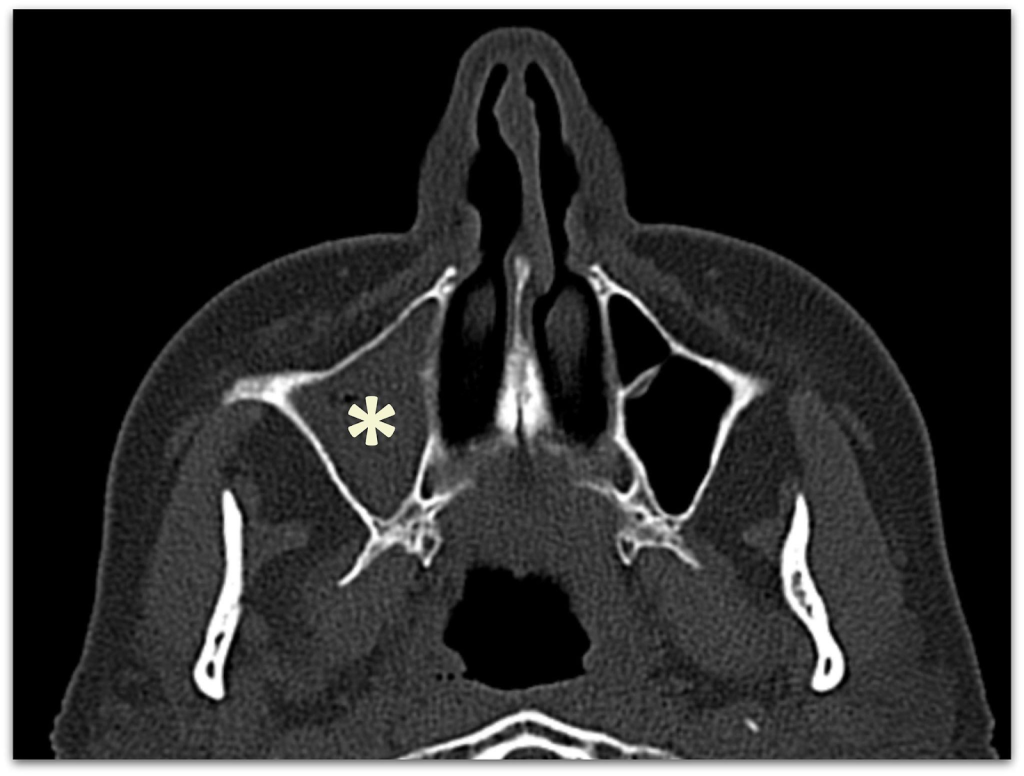

Остіомеатальний комплекс є ключовою зоною, де відбувається дренаж пазух носа. Будь-які аномалії в цій області можуть призвести до обструкції та хронічного гаймориту. Звичайний рентген не може адекватно візуалізувати цю зону через обмежену роздільну здатність і двовимірність зображень. КТ, навпаки, дозволяє чітко бачити цю область, виявляючи навіть незначні зміни, які можуть бути причиною захворювання.

Завантажити дослідженняОстіомеатальний комплекс – це ключова зона, через яку відбувається дренаж пазух.

Навіть невелике звуження тут може спричинити порушення вентиляції, застій слизу та розвиток хронічного гаймориту. Рентген не дозволяє якісно оцінити цю ділянку. КТ – дозволяє чітко побачити навіть мінімальні зміни.

Викривлення носової перегородки є ще однією поширеною проблемою, яка може спричинити або погіршити гайморит. Хоча рентген може виявити значні викривлення, він не здатний точно оцінити їх вплив на дренаж пазух. КТ забезпечує детальну оцінку ступеня викривлення та його впливу на навколишні структури.